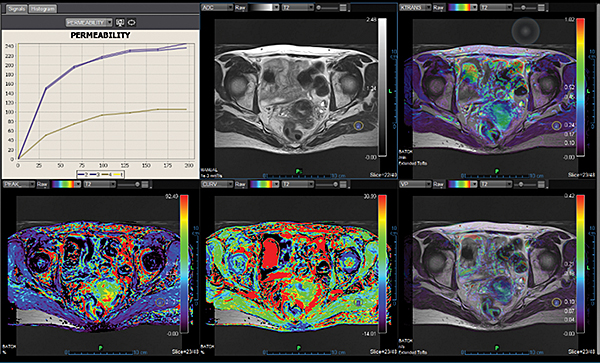

Додаток Female Pelvis.

Додаток Female Pelvis аналізує патологічні морфологічні зміни тазових органів у жінок (яєчники, матка, тазове дно). За кілька кліків можна отримати точні показники: автоматичне обчислення дифузії для швидкої якісної оцінки змін у вказаних ділянках.